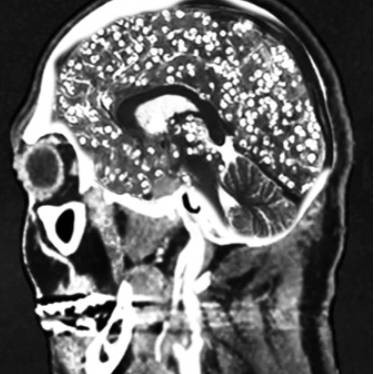

!['돼지고기 촌충'이라 불리는 갈고리촌충의 유충은 혈액을 타고 뇌에 침범해 두통과 발작을 일으키기도 한다. /사진= 유튜브 Chubbyemu]](https://img1.daumcdn.net/thumb/R658x0.q70/?fname=https://t1.daumcdn.net/news/202503/29/moneytoday/20250329132948792hmwg.jpg)

'기생충이 몸 안에 들어오면 음식물을 대신 먹어 살이 빠질 것'이란 속설이 있습니다. 지난해 체중 감량에 어려움을 겪던 미국의 20대 여성이 기생충 알이 든 캡슐을 먹고 다이어트하려다 뇌·목·얼굴·혀·간·척추 등에 기생충이 퍼져 끔찍한 부작용에 시달렸다는 사연이 전해졌습니다. 또 2011년 중국의 한 여대생은 취업난에 시달리던 중 다이어트를 위해 회충알을 다량 섭취해 병원에 실려 갔는데요. 그는 '부화하지 않은 회충의 알을 먹으면 다이어트에 효과가 있다'는 말을 믿고 먹었다가 뱃속에서 회충이 한꺼번에 부화한 것으로 드러났습니다.